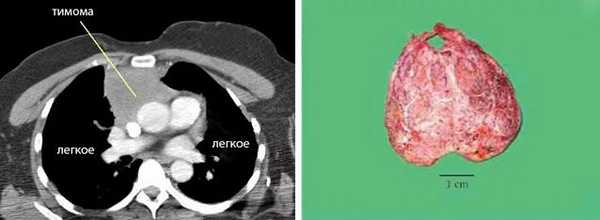

На рентгенограмме грудной клетки тимома имеет вид объемного образования неправильной формы, расположенного в переднем средостении. КТ грудной клетки значительно расширяет объем информации, полученный при первичной рентгендиагностике и в ряде случаев позволяет поставить морфологический диагноз. Уточнение локализации и взаимоотношения новообразования с соседними органами при КТ средостения позволяет в дальнейшем выполнить трансторакальную пункцию опухоли средостения, что чрезвычайно важно для гистологического подтверждения диагноза и верификации гистологического типа тимомы.

Маленькие опухоли лучше диагностировать с помощью более точной КТ. Также компьютерную томографию проводят в тех случаях, когда невозможно исключить опухоль вилочковой железы или миастению. В таких случаях тимома имеет вид овального новообразования, занимающего часть переднего средостения. В ней могут обнаруживаться кальцинаты и кисты.

Благодаря КТ дополнительно удается установить характер связи новообразования с крупными кровеносными сосудами, а также обнаружить метастазы в плевральной полости и перикарде.

Дифференциальная диагностика между гиперплазией и тимомой (рис.3-7) небольших размеров заключается в выявлении новообразования, локально выходящего за контур железы накапливающего контрастное вещество в разные фазы контрастирования отлично от неопухолевой ткани вилочковой железы.